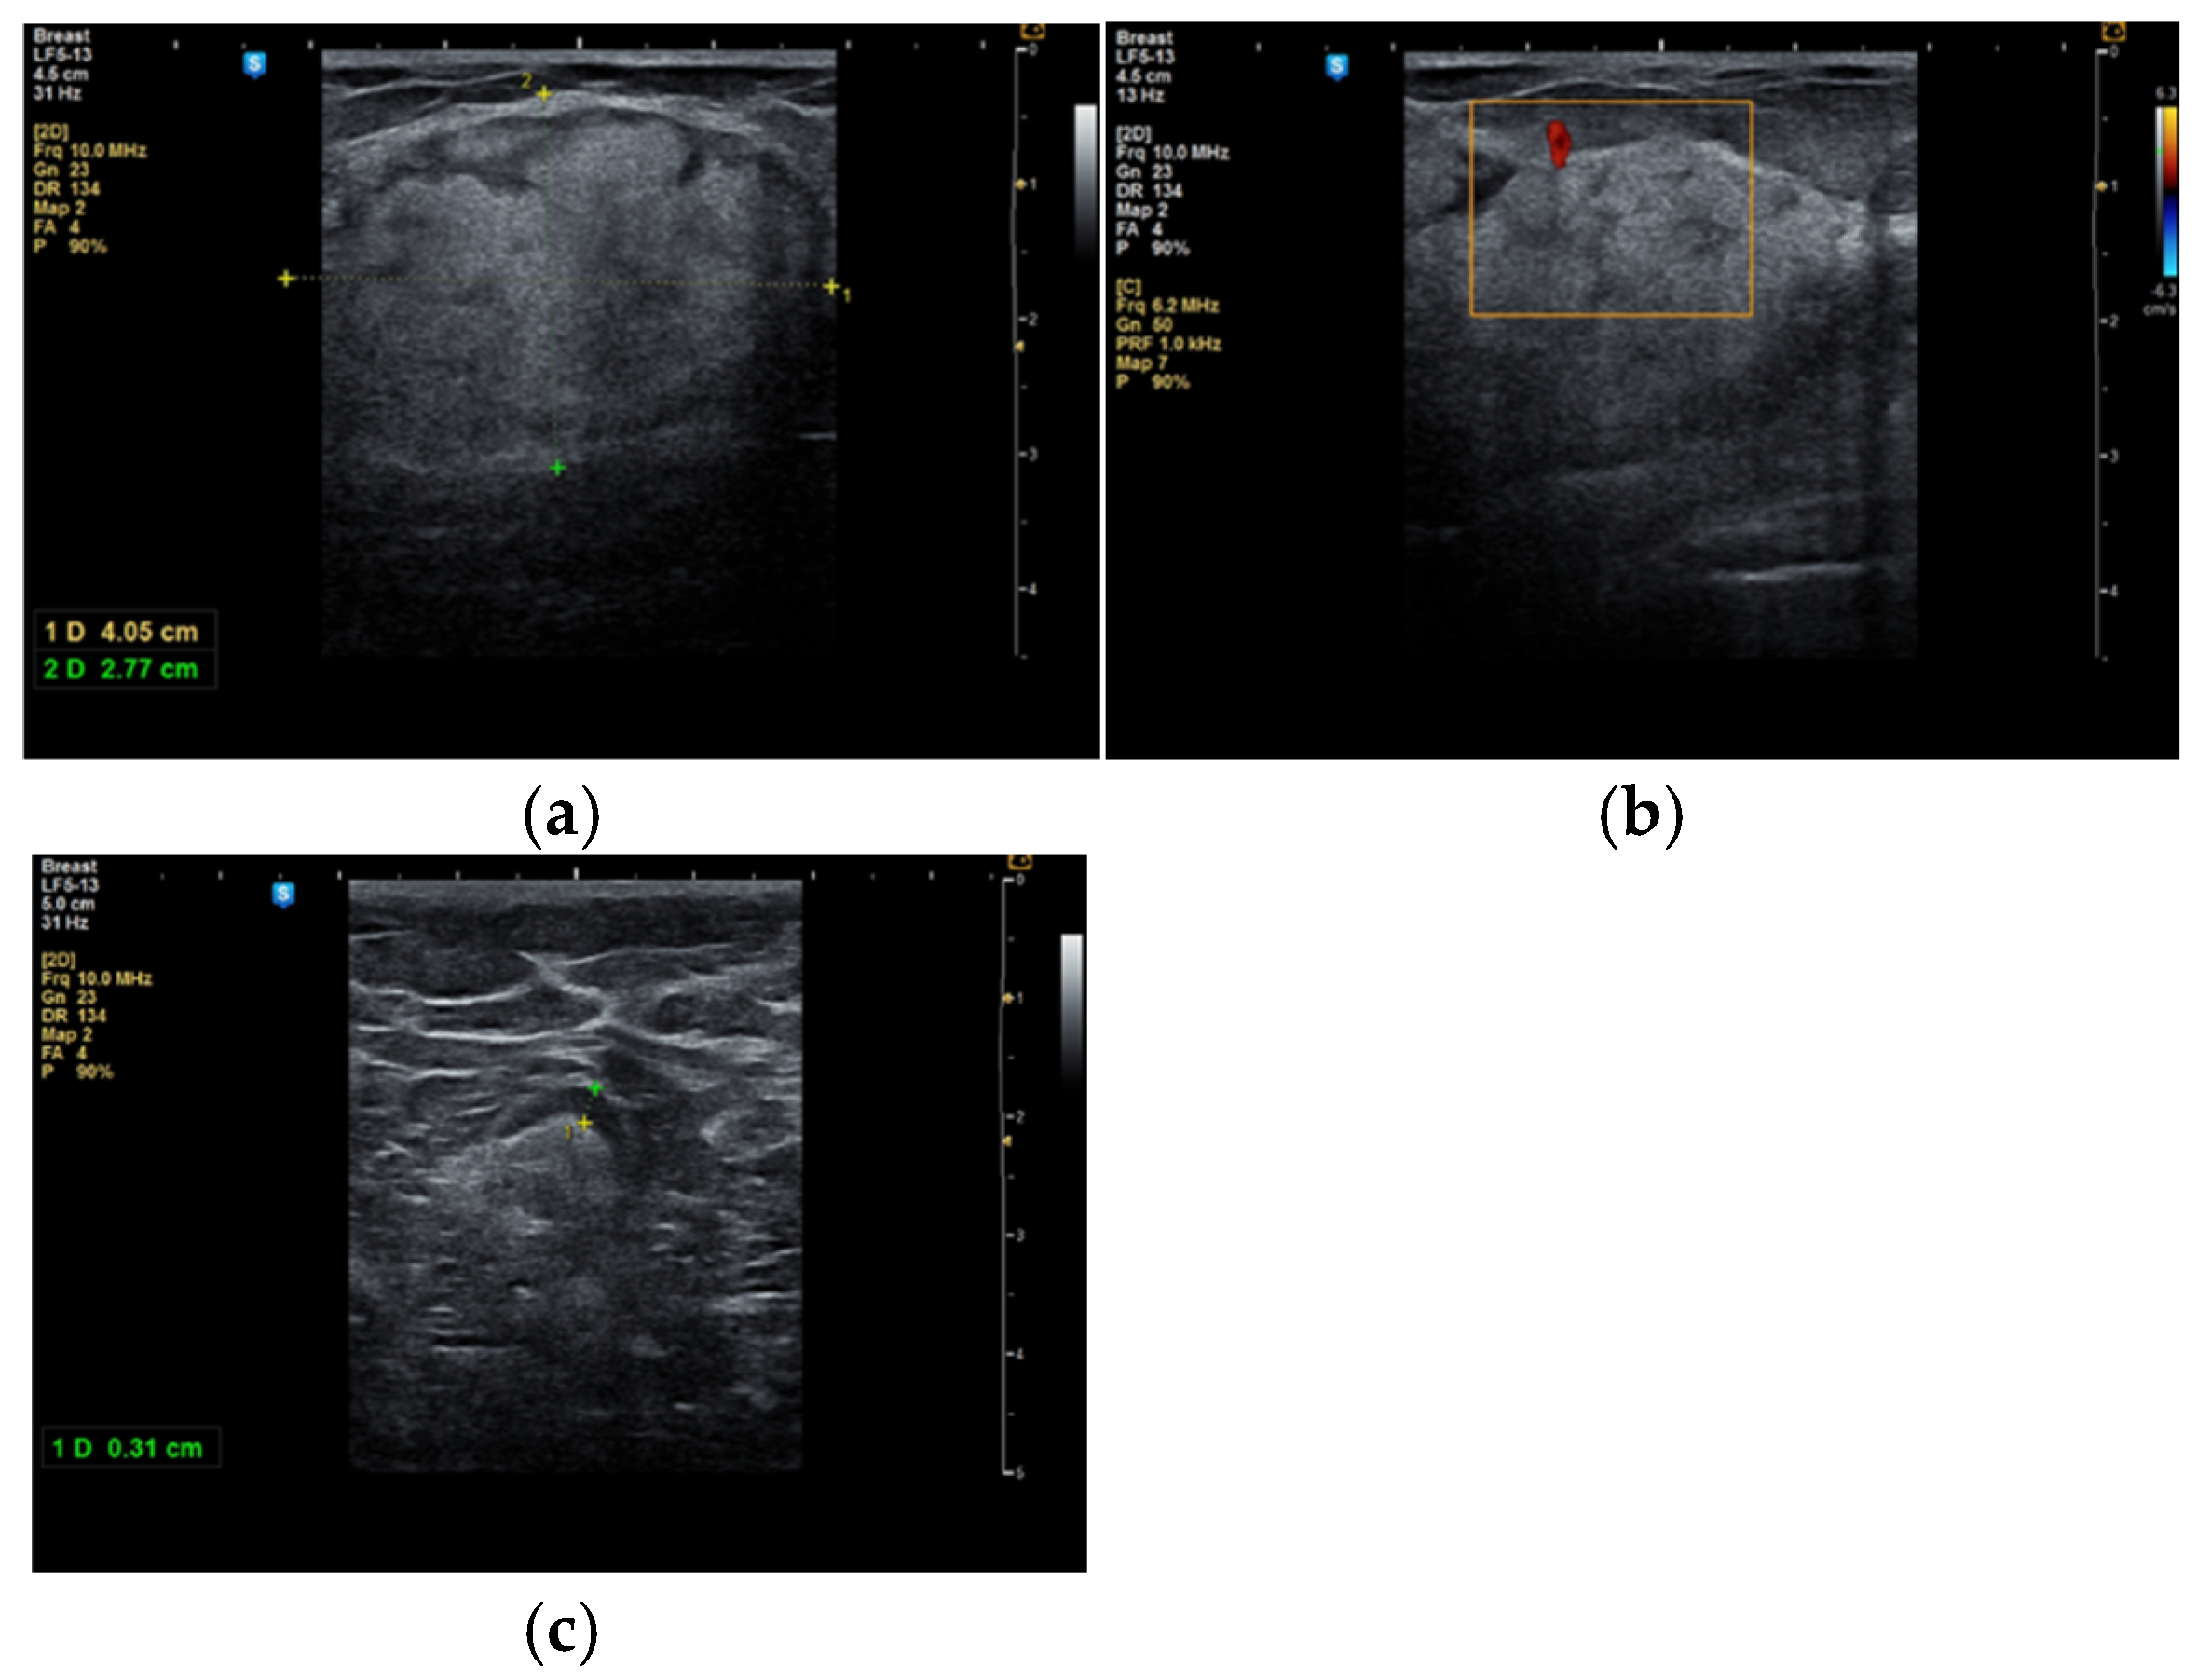

During the study period, a case initially suspected to be a hamartoma on MRI, with peripheral vessel involvement and benign axillary adenopathy, was encountered. However, an ultrasound examination established the diagnosis of a 5 × 3 cm lipoma in a 52-year-old woman, despite the tumor’s rapid growth over the course of one year (Figure 4a,b). The lipoma consisted solely of homogeneous adipose tissue, appearing hypoechoic on the ultrasound exam, with few thin striations. This case is particularly significant as it highlights the diagnostic challenges associated with differentiating between breast hamartomas and lipomas, especially in instances where rapid tumor growth is observed over one year.

Figure 4.

Breast lipoma in a 52-year-old woman (a) macroscopic pathological aspect; (b) ultrasound exam—hypoechoic aspect with thin striations.